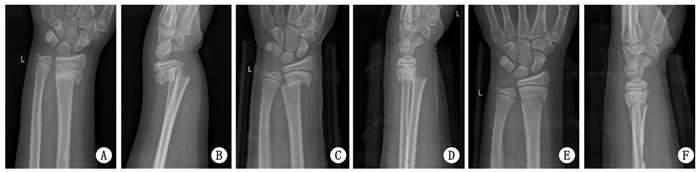

2 结果重复整复后的掌倾角、尺偏角、桡骨长度, 明显好于治疗前及首次整复后, 差异具有统计学意义(P < 0.05), 见表 1.所有患者获得随访, 骨折均愈合, 无神经及血管损伤, 无骨筋膜室综合发生.治疗后6个月, Gartland-Werley腕关节评分, 优14例, 良17例, 可3例, 差1例, 优良率达到88.57%. Knirk-Jupiter关节炎分级评价, 0级27例; 1级5例; 2级2例; 3级1例.典型病例修复前后X线片见图 1~3.

| A、B为治疗前, C、D为首次复位后, E、F为再次复位后 图 1 男性42岁患者, 右侧桡骨远端骨折治疗后骨折复位变化 |